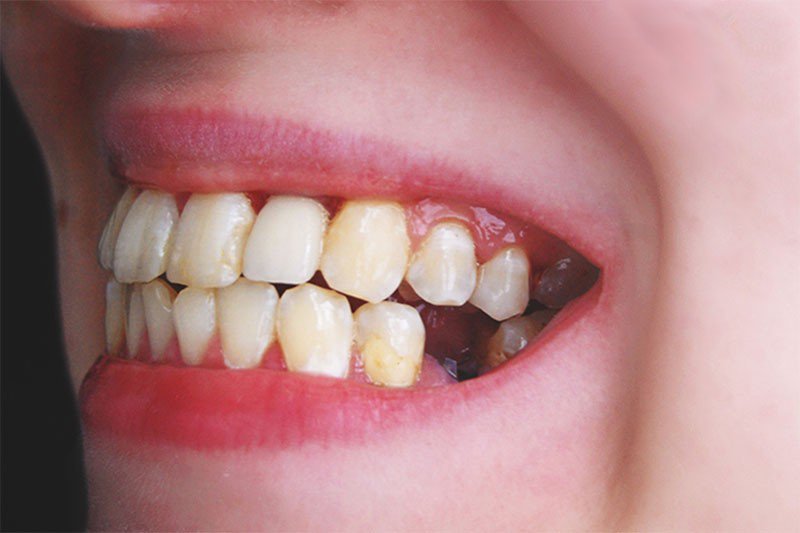

Ảnh hưởng đến thẩm mỹ khuôn mặt

Tiêu xương vùng răng số 6 khiến vùng má hóp lại, da chảy xệ, khuôn mặt già hơn tuổi.

Ở phụ nữ, đây là nguyên nhân khiến nếp nhăn quanh miệng và rãnh cười sâu hơn.